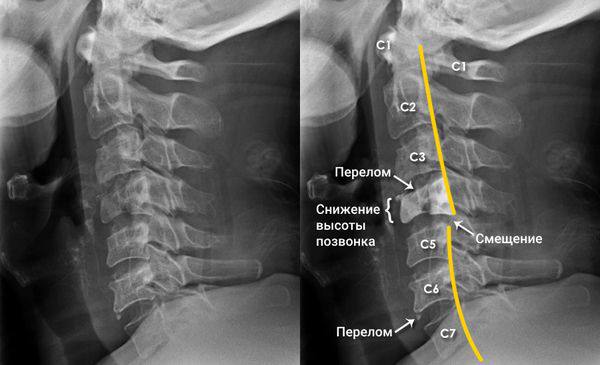

Распространенный миф о том, что сохранение двигательной активности после падения или взрыва гарантирует отсутствие повреждений позвоночника, является одним из наиболее опасных заблуждений в тактической медицине. Согласно данным медицинской статистики, собираемой в зоне СВО, у 35% раненых с подтвержденными переломами позвоночника в первые часы после травмы сохранялась полная или частичная двигательная активность. Этот феномен объясняется механической стабильностью некоторых типов повреждений и временным характером неврологических нарушений. Патофизиологической основой опасности данного мифа является концепция нестабильных переломов позвоночника, которые могут не проявляться немедленной неврологической симптоматикой, но приводят к катастрофическим последствиям при отсутствии иммобилизации.

Механизм отсроченного повреждения спинного мозга включает несколько патогенетических компонентов. Формирование эпидуральной гематомы прогрессирует в течение 2-6 часов после травмы, вызывая постепенную компрессию нервных структур. Отек спинного мозга нарастает в течение первых суток, усугубляя ишемию в зоне повреждения. Особую опасность представляют нестабильные переломы с повреждением связочного аппарата, когда малейшее движение может вызвать смещение отломков и полный перерыв спинного мозга. Статистика показывает, что 25% тяжелых неврологических нарушений при травмах позвоночника развиваются не в момент травмы, а во время транспортировки или оказания помощи.

Клиническая картина может включать минимальные симптомы, такие как локальная болезненность при пальпации (85% случаев), напряжение паравертебральных мышц (70%) и незначительные чувствительные нарушения (45%). Особенностью взрывных повреждений является феномен "скрытой нестабильности", когда при сохранении целостности переднего опорного комплекса происходит повреждение задних структур позвоночника. По данным исследований, у 60% таких пострадавших отсутствуют явные неврологические нарушения в первые 3 часа после травмы.